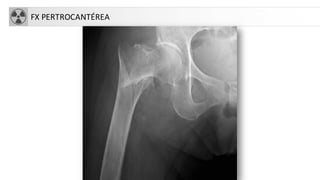

FX EXTREMO PROXIMAL DE FÉMUR

CLASIFICACIÓN

• Fracturascapitales: raras, asociadas a

luxación

• Fracturascervicales (intraarticulares)

1. subcapitales.

2. transcervicales

3. basicervicales

• 4. Fracturastrocantereas:

• cervicotrocantereas

• pertrocantereas(+frecuente)

• 5. Fracturassubtrocantereas

• Aisladas de trocanter mayor

• Aisladas de trocánter menor

FX PERTROCANTÉREA